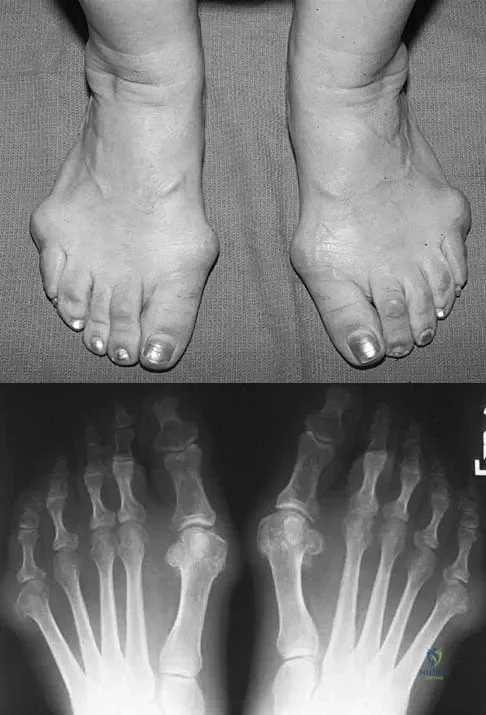

Question 64

Figures 5a and 5b show the clinical photograph and radiograph of a patient who has difficulty wearing shoes and has persistent symptoms medially and laterally at the first and fifth metatarsophalangeal joints. Because shoe modifications have failed to provide relief, management should now consist of

Explanation